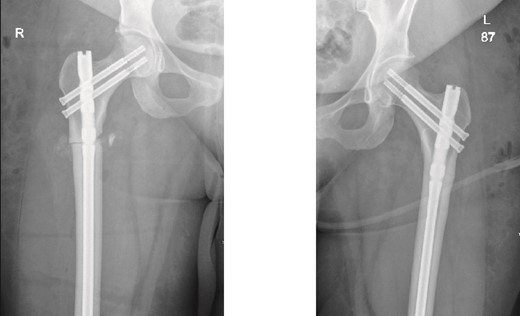

The patient was seen in the clinic at 2 weeks, 6 weeks, and 6 months post-surgery. She was doing well, reporting only mild pain. She was fully weight-bearing with the assistance of a cane and had good range of motion (Figs 3 and 4).

6-weeks follow-up anteroposterior (AP) view of the right and left femurs after CRIF with IM nail.

6-months follow-up anteroposterior (AP) view of the right and left femurs after CRIF with IM nail.

On the contralateral side, the fracture was a cortical stress line, and a prophylactic nailing was performed. As reported in the literature, the most common approach for incomplete AFFs is surgical fixation, as these fractures are more likely to progress to complete fractures [7]. Previously reported cases managed prophylactically have shown full radiographic union, with patients being pain-free ~8 months post-surgery [8]. In contrast, our patient achieved full clinical union just 2 months postoperatively, mobilizing independently with a cane for support and being pain-free.